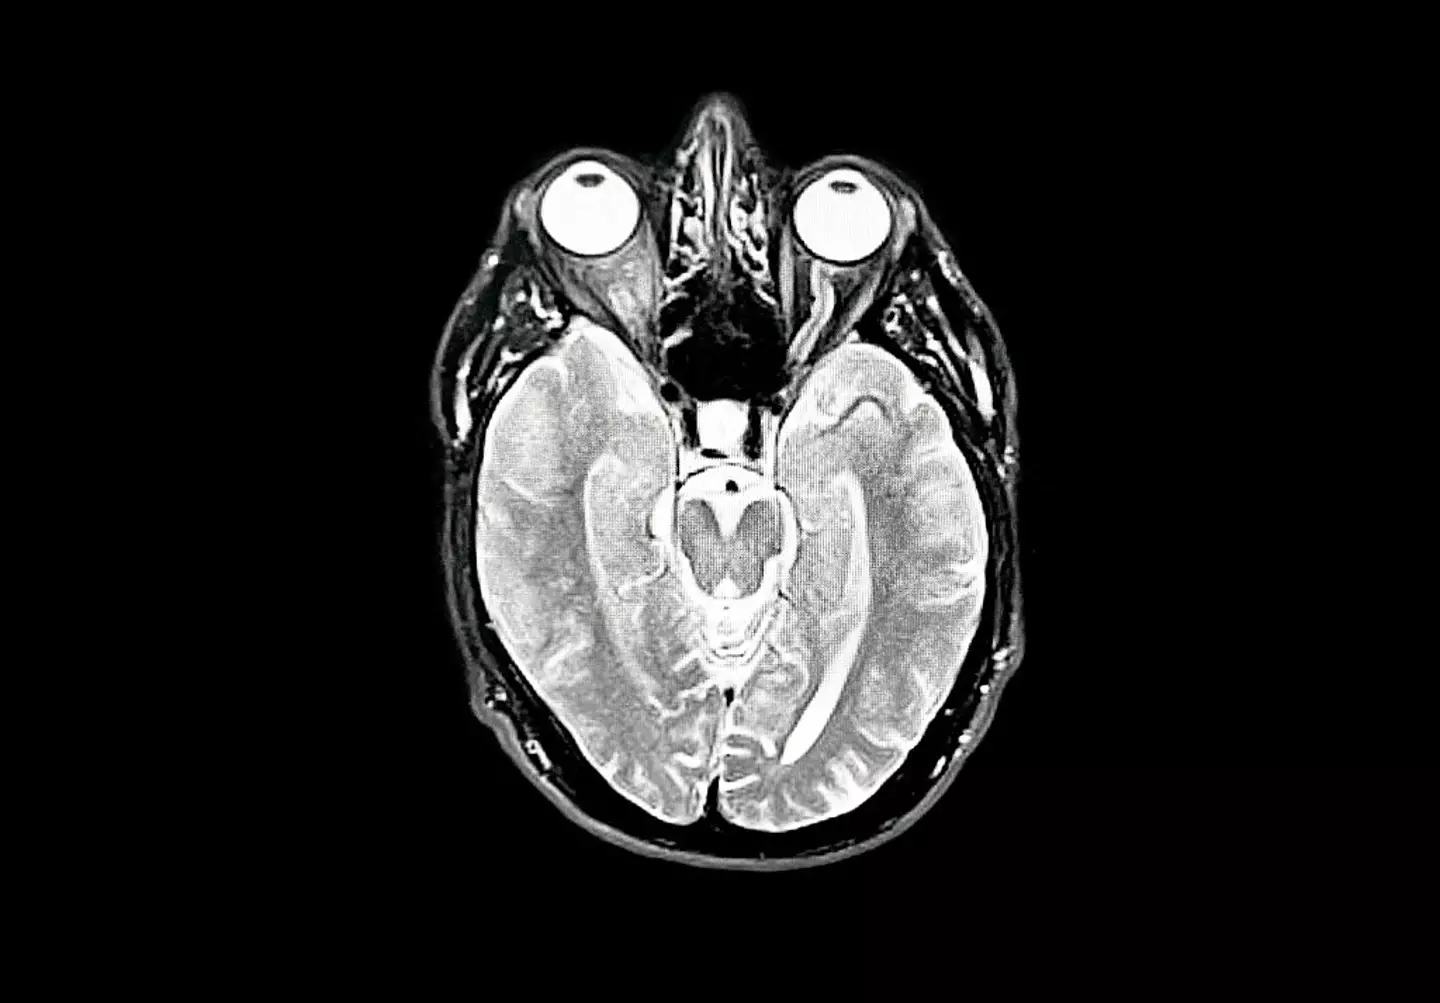

With the condition being neurodegenerative, meaning cells in the brain lose their function and die, it is now believed to have an impact on our senses.

University of West Scotland's expert in young-onset dementia, Molly Murray, wrote for The Conversation that many patients complain of having experienced problems with their eyesight prior to receiving their diagnosis.

She penned: "Research shows that for around one third of people with young-onset Alzheimer’s disease [which is the most common form of dementia], the earliest symptoms they had were problems with coordination and vision changes."